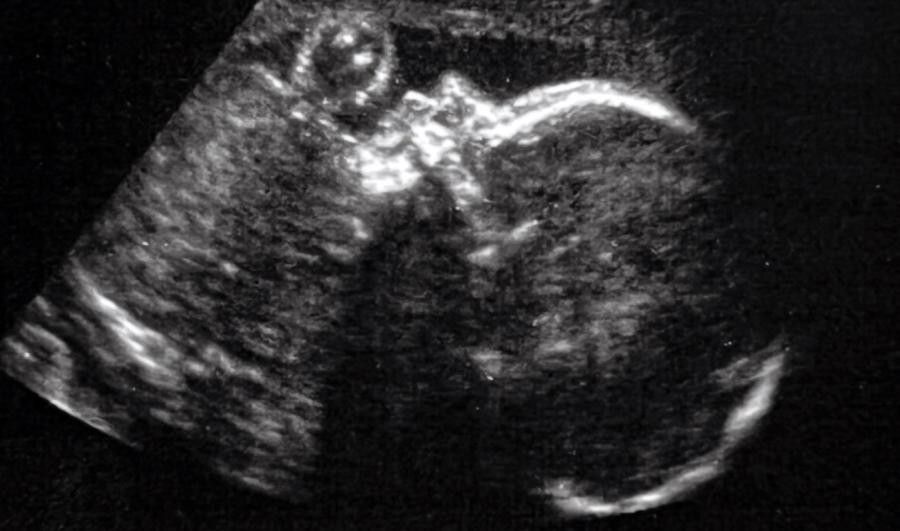

When Kenyatta found out she was pregnant with her fourth child, she had no reason to worry about any complications. The pregnancy was deemed low risk. She was receiving excellent prenatal care and felt just fine. She saw her doctor regularly and had her ultrasounds right on schedule.

Everything was routine, all checks in order, until about 30 weeks.

After that ultrasound, Kenyatta’s doctor sat her down and told her that she had seen a malformation. The scan showed that the baby’s heart was abnormally large. “She shared with me that something wasn’t right in terms of the baby’s brain,” Kenyatta said.